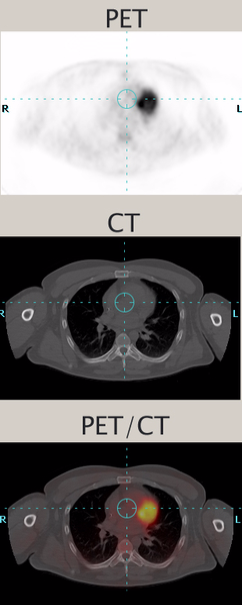

When disease strikes, the biochemistry of cells and tissue changes. In cancer, for example, cells begin to grow at a much faster rate. In one continuous whole-body scan, PET/CT captures images of changes in the body’s metabolism caused by actively growing cancer cells and provides a detailed picture of the body’s internal anatomy that reveals the size, shape and exact location of the abnormal cancerous growths.

The CT and PET images are assembled by the computer into a 3-D image of the patient’s body. If an area is cancerous, the signals will be stronger there than in surrounding tissue, since more of the radiopharmaceutical will be absorbed in those areas. Each imaging modality can be viewed independently of the other without compromise, or used in concert for complementary functional and anatomic diagnosis. PET/CT is a highly sensitive procedure that aids in the detection of small cancerous tumors and subtle changes in the brain and heart. This enables physicians to identify and treat these diseases earlier and more accurately.